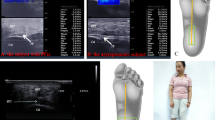

Chronic plantar fasciitis was diagnosed based on clinical symptoms, physical examinations and imaging studies. All the patients had the typical symptoms, such as morning heel pain.

Table 4 summarizes the 10 predictive factors. Univariate analysis of all independent factors for ESWT was done in groups with and without MSCT. Among all the 10 factors, higher VAS score (short-term increase of pain severity when the patient took first steps in the morning or had plantar fascia spur) increased the odds of MCST (p < 0.05). These three factors (VAS, presence of heel spur and duration of symptoms) were then put into the ANNs model. Importance, normalized Importance and value of the 10 independent variables are illustrated in Table 5. The interrelationships between predictor variables (input nodes), hidden variables (5 items in 1 hidden layer), and MSCT are shown in Fig. 1.

For VAS, heel spur and symptom duration, the diagnosis sensitivity was 84.3%, 87.9% and 61.4%, respectively; the diagnosis specificity was 35.7%, 37.4% and 22.3%, respectively. The result of sensitivity and specificity both demonstrated a high accuracy. The positive predictive value was 69%, 72% and 57%, respectively. The negative predictive value was 82%, 84% and 59%, respectively. The AUC was 0.738, 0.882 and 0.520, respectively, which demonstrated a good discrimination. Table 6 and Fig. 2 demonstrated the Area under ROC curve, predictive values of ANN models and three individual parameters to predict the achievement of MCST.